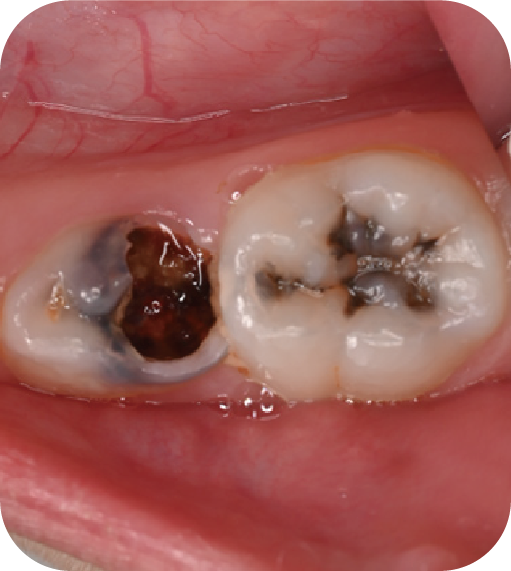

后磨牙,也就是大牙咬合面上凹凸不平的裂隙,這就是“窩溝”。窩溝有很多形狀,有的是狹長(zhǎng)的裂隙形狀,還有的在牙齒深處又會(huì)分成幾條小溝。這些地方用牙刷很難深入清潔,于是就成了衛(wèi)生死角,細(xì)菌特別喜歡在里面生存,不斷產(chǎn)酸腐蝕牙齒,蛀牙就這樣產(chǎn)生了。如果我們用窩溝封閉把這些衛(wèi)生死角封起來(lái),那既可以杜絕食物和細(xì)菌進(jìn)入窩溝內(nèi),也可以讓窩溝處的清潔變得更簡(jiǎn)單,這就是做窩溝封閉的目的。同時(shí)它也是世界衛(wèi)生組織、國(guó)家衛(wèi)健委都推薦的防齲方法。